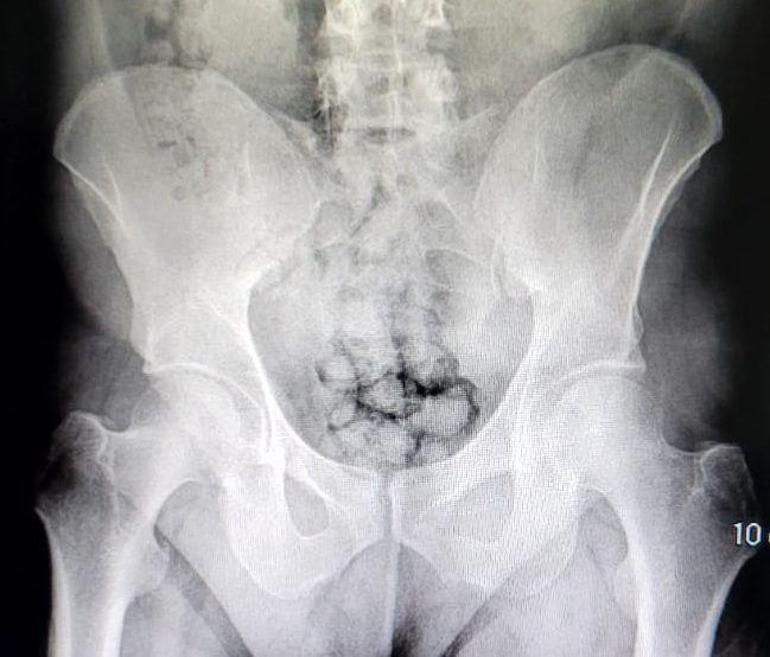

Şüphelilerin bulunduğu araç durduruldu. Muayene edilmek üzere Kayseri Devlet Hastanesi'ne getirilen 2 şüphelinin röntgenleri çekildi. Röntgen çekimi sonrası şüphelilerin midesinde yaklaşık 80 kapsül içinde metamfetamin olduğu tespit edildi. Uyuşturucular sağlık ekiplerince yapılan tedavinin ardından çıkarıldı.